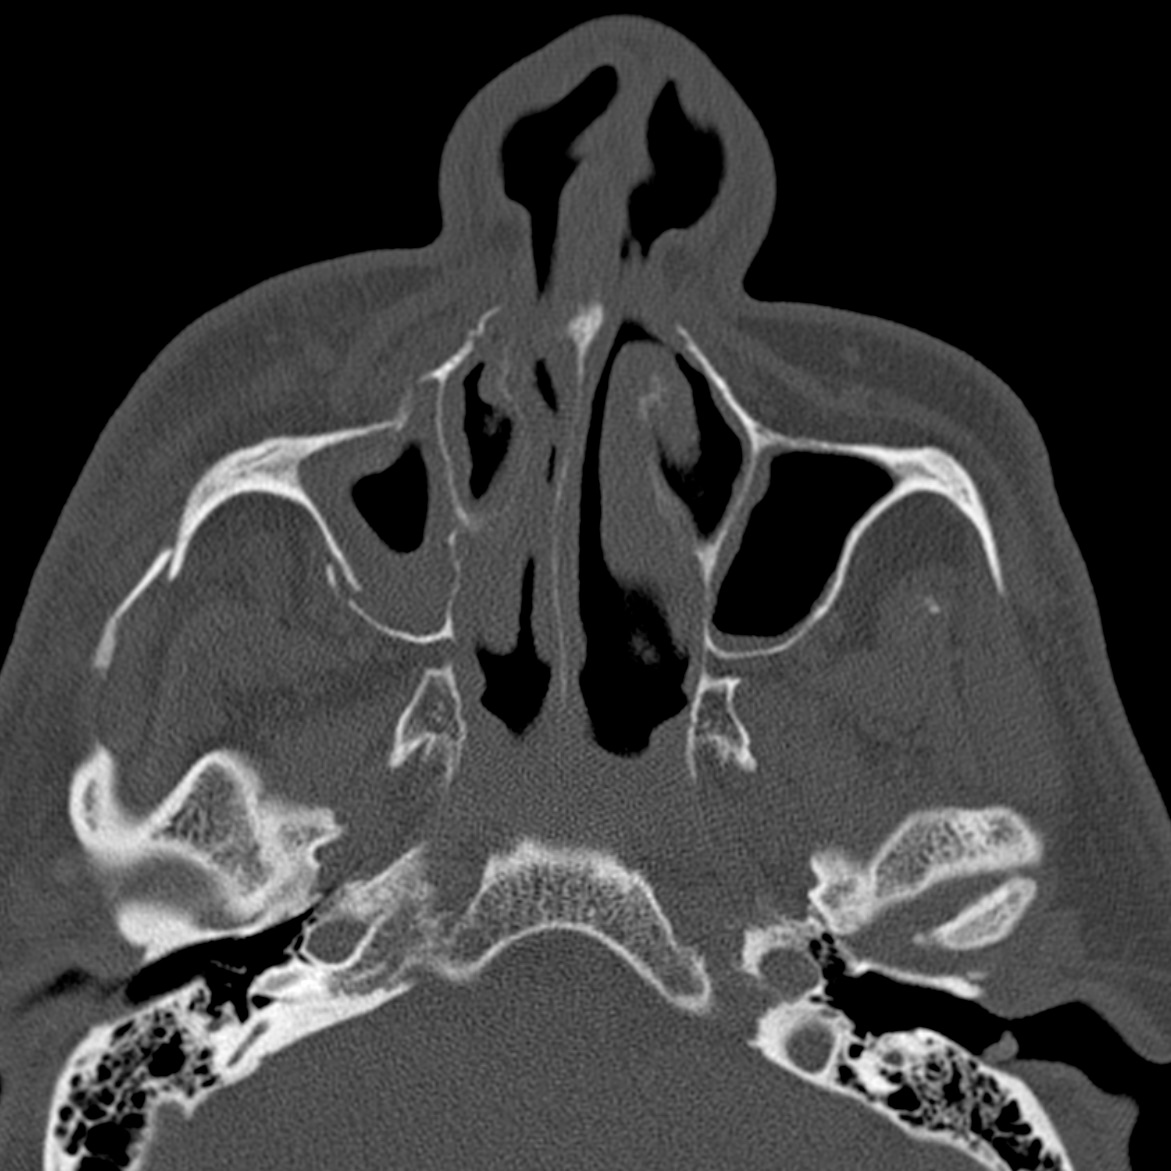

What is this facial fracture pattern?QuestionAlexander BaxterApr 03, 20231Share Click here for answer and discussionThanks for reading RadNotes! Subscribe for free to receive new posts and support my work.SubscribeShare RadNotesPreviousNext